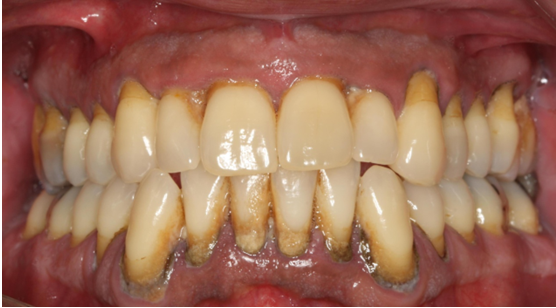

15. Θεραπεία χρόνιας περιοδοντίτιδας σε καπνιστή

Ο ασθενής ηλικίας 50 ετών παρουσίαζε περιοδοντική νόσο προχωρημένης βαρύτητας και ήταν βαρύς καπνιστής. Ανέφερε πόνο στα ούλα, αιμορραγία και έντονη κακοσμία. Παράλληλα με την περιοδοντική θεραπεία, δόθηκε έμφαση στη μείωση του καπνίσματος. Στην κλινική εικόνα κατά την επανεξέταση παρατηρείται απουσία φλεγμονής.

ΑΡΧΙΚΗ ΚΛΙΝΙΚΗ ΕΙΚΟΝΑ

ΤΕΛΙΚΗ ΚΑΤΑΣΤΑΣΗ